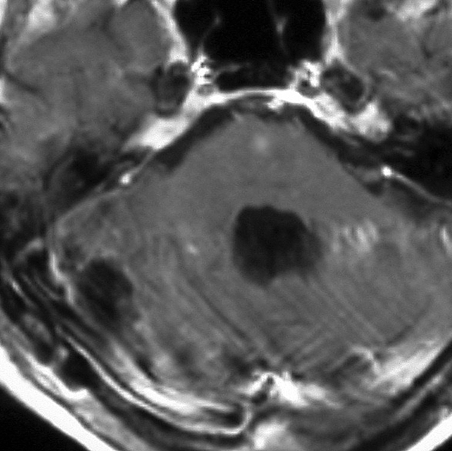

- MRIでは,のう胞(袋に水がたまったようなもの)を高頻度に認めます

- 腫瘍の本体は造影剤で増強効果をうけて白く丸く映ります

- 腫瘍はたいてい丸くてはっきりした形にみえます

左小脳にできた小さな のう胞性血管芽腫です。矢印の先にある小さな塊だけが腫瘍で周囲は腫瘍から染み出した液体が溜まっています(のう胞といいます)。右側は血管撮影とMRIを組み合わせた画像で,腫瘍に動脈が流入しているのが見えます。